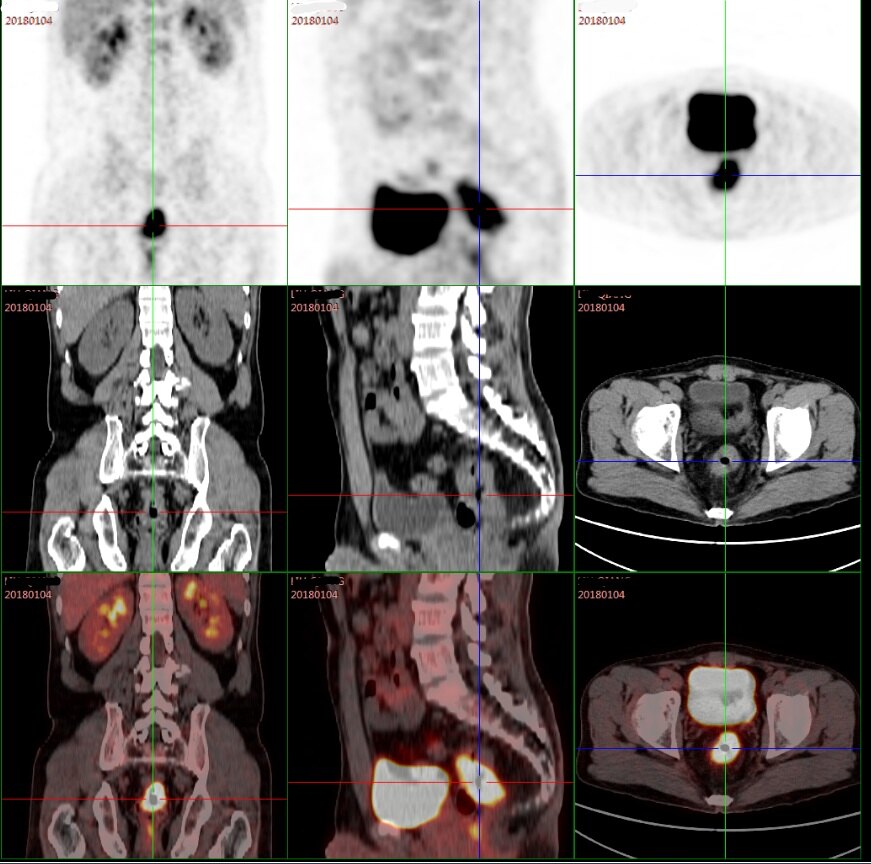

大肠壁增厚. 肠壁厚度可超过 2 cm, 这时如果口服高密度造影剂 , 肠腔内造影剂会嵌入肿胀的黏膜皱襞间 , 高密度的造影剂和低密度增厚的皱襞在CT 上形成 “手风琴征”提示严重的黏膜下水肿 。 病变累及…. 大肠癌是我国常发的癌症。 复发率比较高,而早期发现复发的癌灶,除了临床常规的血液检查外,影像学检查是必不可少的,常用的有超声, ct 和磁共振,而 fdg-pet 对于病灶,尤其是对于大肠癌的诊断和良恶性鉴别诊断起着重要的作用。 pet/ct 相对于其他的影像学检查来说,相对比较新,对于很多. 膀胱充盈状态:壁明显增厚,层次不清晰,回声减低。动态扫查显示膀胱内壁毛糙、不光整,小房、小梁样结构增生,膀胱内壁为弥漫性环状气体回声围绕,前壁显示清晰,后壁因气体反射无法显示,转换体位及探头加压可见气体流动征象(图 2 和视频 1)。.